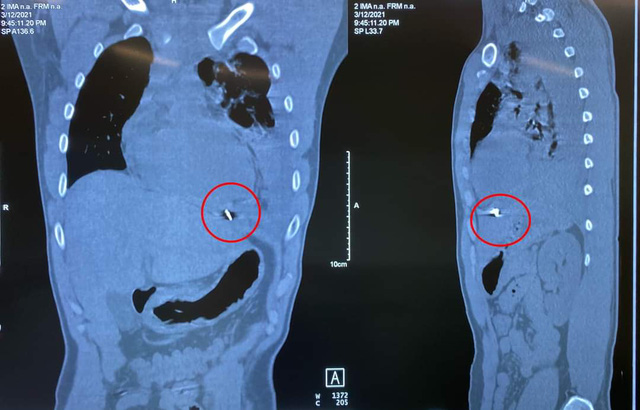

Theo lời kể của bệnh nhân, chiều ngày 12/3, khi bệnh nhân đang chẻ củi, không may bị mảnh kim khí văng bắn vào ngực trái. Sau tai nạn, bệnh nhân thấy đau ngực, khó thở và được đưa cấp cứu tại bệnh viện tuyến dưới. Tại đây bệnh nhân đã được sơ cứu và chụp CT lồng ngực thấy có nhiều máu trong khoang màng phổi trái và chuyển bệnh nhân lên Bệnh viện TWQĐ 108.Bệnh nhân được chuyển đến Bệnh viện TWQĐ 108 trong tình trạng khó thở cả hai thì, nhịp tim nhanh, huyết áp xu hướng tụt thấp. Bệnh nhân được thở oxy, theo dõi sát tình trạng hô hấp, đồng thời khảo sát bằng siêu âm và chụp CT lồng ngực: phát hiện tràn máu màng phổi trái mức độ nhiều, kèm theo xẹp phổi trái thụ động, có mảnh kim khí nằm trong cơ hoành, mặt dưới tâm thất trái.TS. Ngô Vi Hải – Chủ nhiệm Khoa Ngoại lồng ngực đánh giá: đây là một ca tổn thương phức tạp, chảy máu nhiều trong khoang màng phổi , không tương xứng với tổn thương nhu mô phổi. Ngoài ra có hình ảnh dịch màng ngoài tim nghi ngờ tổn thương tim, tiên lượng rất nặng, nguy cơ tiến triển thành ép tim cấp.

TS Ngô Vi Hải đã chỉ định mổ cấp cứu và chỉ đạo chuẩn bị đầy đủ tất cả các phương án về phẫu thuật, gây mê, hồi sức. Ngay sau đó, bệnh nhân được phẫu thuật cấp cứu để xử trí cầm máu và lấy dị vật.Các bác sĩ đã tiến hành phẫu thuật mở ngực đường bên vào khoang màng phổi trái. Trong khoang màng phổi trái và màng tim có gần 1500ml máu và máu đông. Dị vật là 1 mảnh kim khí dài khoảng 1cm có cạnh sắc, làm rách mặt trước màng tim và găm vào mặt hoành của màng tim. Tâm thất trái đè lên dị vật và bị cạnh sắc của dị vật cứa rách gây chảy máu vào khoang màng tim và qua lỗ thủng mặt trước màng tim tràn vào khoang màng phổi trái.